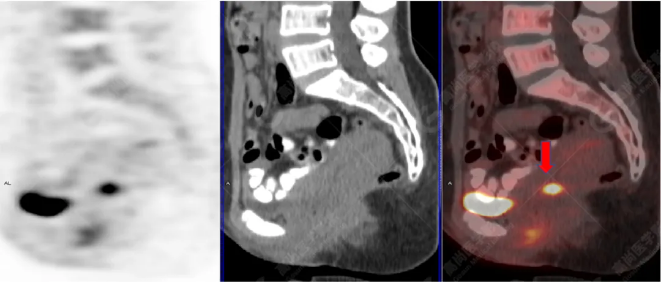

病史摘要:女性 36歲 因左后肋區(qū)疼痛1月余查體,無(wú)其他不適。PET/CT影像圖

左胸一后肋溶骨性骨質(zhì)破壞,周圍伴軟組織形成,F(xiàn)DG代謝增高,SUVmax為10.9。

找到引起骨痛病灶,病因:原發(fā)?轉(zhuǎn)移?感染?

最終診斷:宮頸癌伴肋骨單發(fā)骨轉(zhuǎn)移。